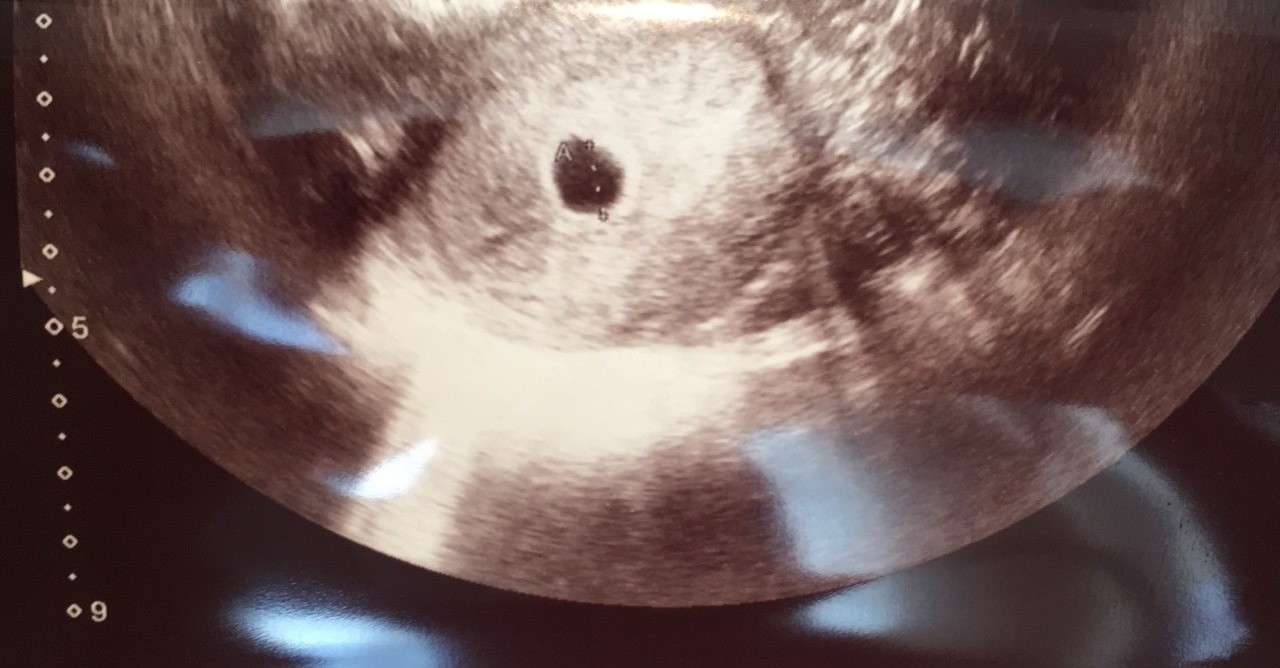

妊娠4週3日 4w3d の超音波 エコー 写真